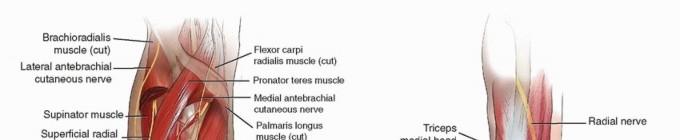

العصب الكعبري (Radial Nerve): الأهمية والمخاطر

يُعد العصب الكعبري أهم هيكل عصبي يمر بالقرب من منتصف عظم العضد. يلتف هذا العصب بشكل حلزوني من الخلف إلى الجانب الخارجي للعضد، داخل ما يُعرف بـ "الميزاب الحلزوني" أو "الميزاب الكعبري". يرافقه الشريان العضدي العميق.

- موقعه: في الجزء العلوي، يقع بين الرأس الإنسي والوحشي لعضلة الترايسبس. في الجزء السفلي، يخترق الحاجز العضلي الوحشي ليصبح أمام اللقيمة الوحشية، وينقسم إلى فروع سطحية (حسية) وعميقة (حركية).

- خطورته: يتعرض العصب الكعبري لخطر الإصابة في حوالي 10-18% من كسور العضد المغلقة. هذه الإصابة قد تؤدي إلى "سقوط الرسغ" (Wrist Drop) وصعوبة في بسط الأصابع. أثناء الجراحة، يجب على الجراحين، مثل الأستاذ الدكتور محمد هطيف ، توخي أقصى درجات الحذر لتحديد العصب وحمايته لتجنب أي إصابة عرضية.

تُظهر هذه الصورة الجانب الخلفي لعظم العضد مع المعالم التشريحية، بما في ذلك مسار العصب الكعبري، وكيفية وضع الشريحة الجراحية لتثبيت الكسر.